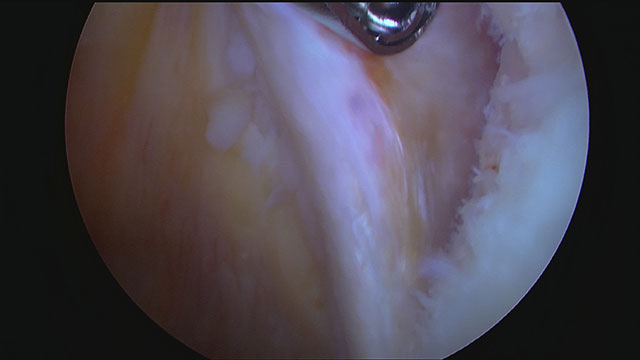

Zunächst wird das Labrum umfassend mobilisiert und das Gewebe sowie der Knochen an der Pfanne angefrischt, so dass eine gute Einheilung gewährleistet ist.